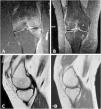

Transient osteoporosis of pregnancy is a rare entity, often underdiagnosed, because it presents mechanical pain that is also characteristic of the adaptive changes in pregnancy. It is more frequent in previously healthy women during the third trimester of pregnancy.8,9 It can occur in 2 forms: systemic and regional. The systemic form mainly affects the trabecular bone and, in particular, the spine. Its prevalence is unknown, since some of its predominant clinical manifestations, such as low back pain, are typical in the course of a normal gestation, due to the mechanical overload inherent to pregnancy.10 The regional form, which predominates in our series of cases, usually settles on load-bearing joints, with the most frequent location in the hip, followed by the knee. Bilateral involvement is more exceptional. Nevertheless, in our case series 50% of the patients had bilateral gonalgia, 25% migratory coxalgia and another 25% postpartum right coxalgia (Figs. 1–4).

MRI is the imaging test indicated to demonstrate the characteristic edema of the bone marrow of the affected joint, as it is sensitive enough to detect it in the first 48¿;hours from the onset of symptoms.13 It shows increased signal intensity in fat-suppressed T2-weighted or STIR images and decreased signal intensity in T1-weighted images,6,8 as observed in the images presented in our case series.